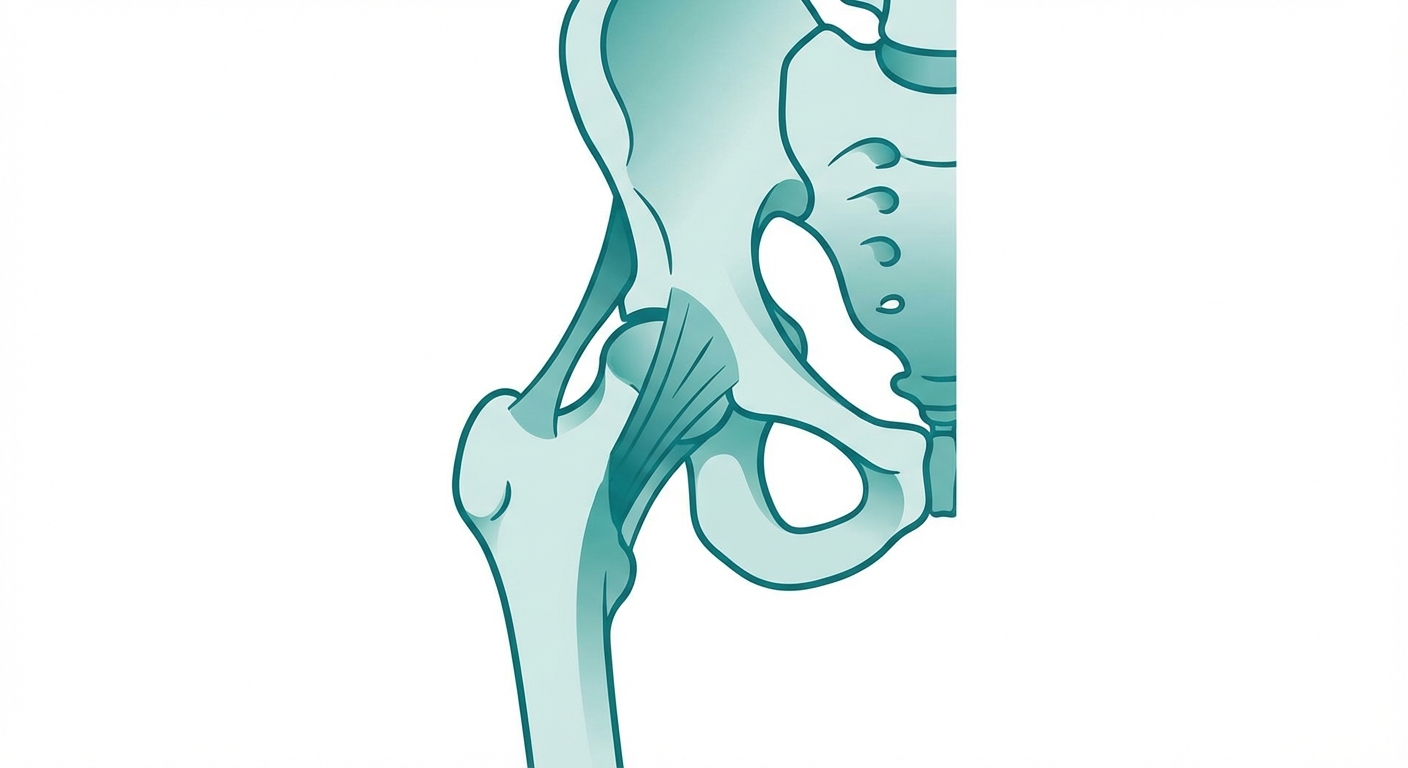

Hip Pain

Hip pain affects how you walk, sit, and sleep. From tight flexors to bursitis to pelvic floor issues, targeted physical therapy exercises can address the root cause and restore comfortable movement.

Hip Pain: Causes, Exercises & Treatment

Hip pain affecting your daily life? Learn the common causes, best exercises for relief, proven treatments, and when it's time to see a professional.